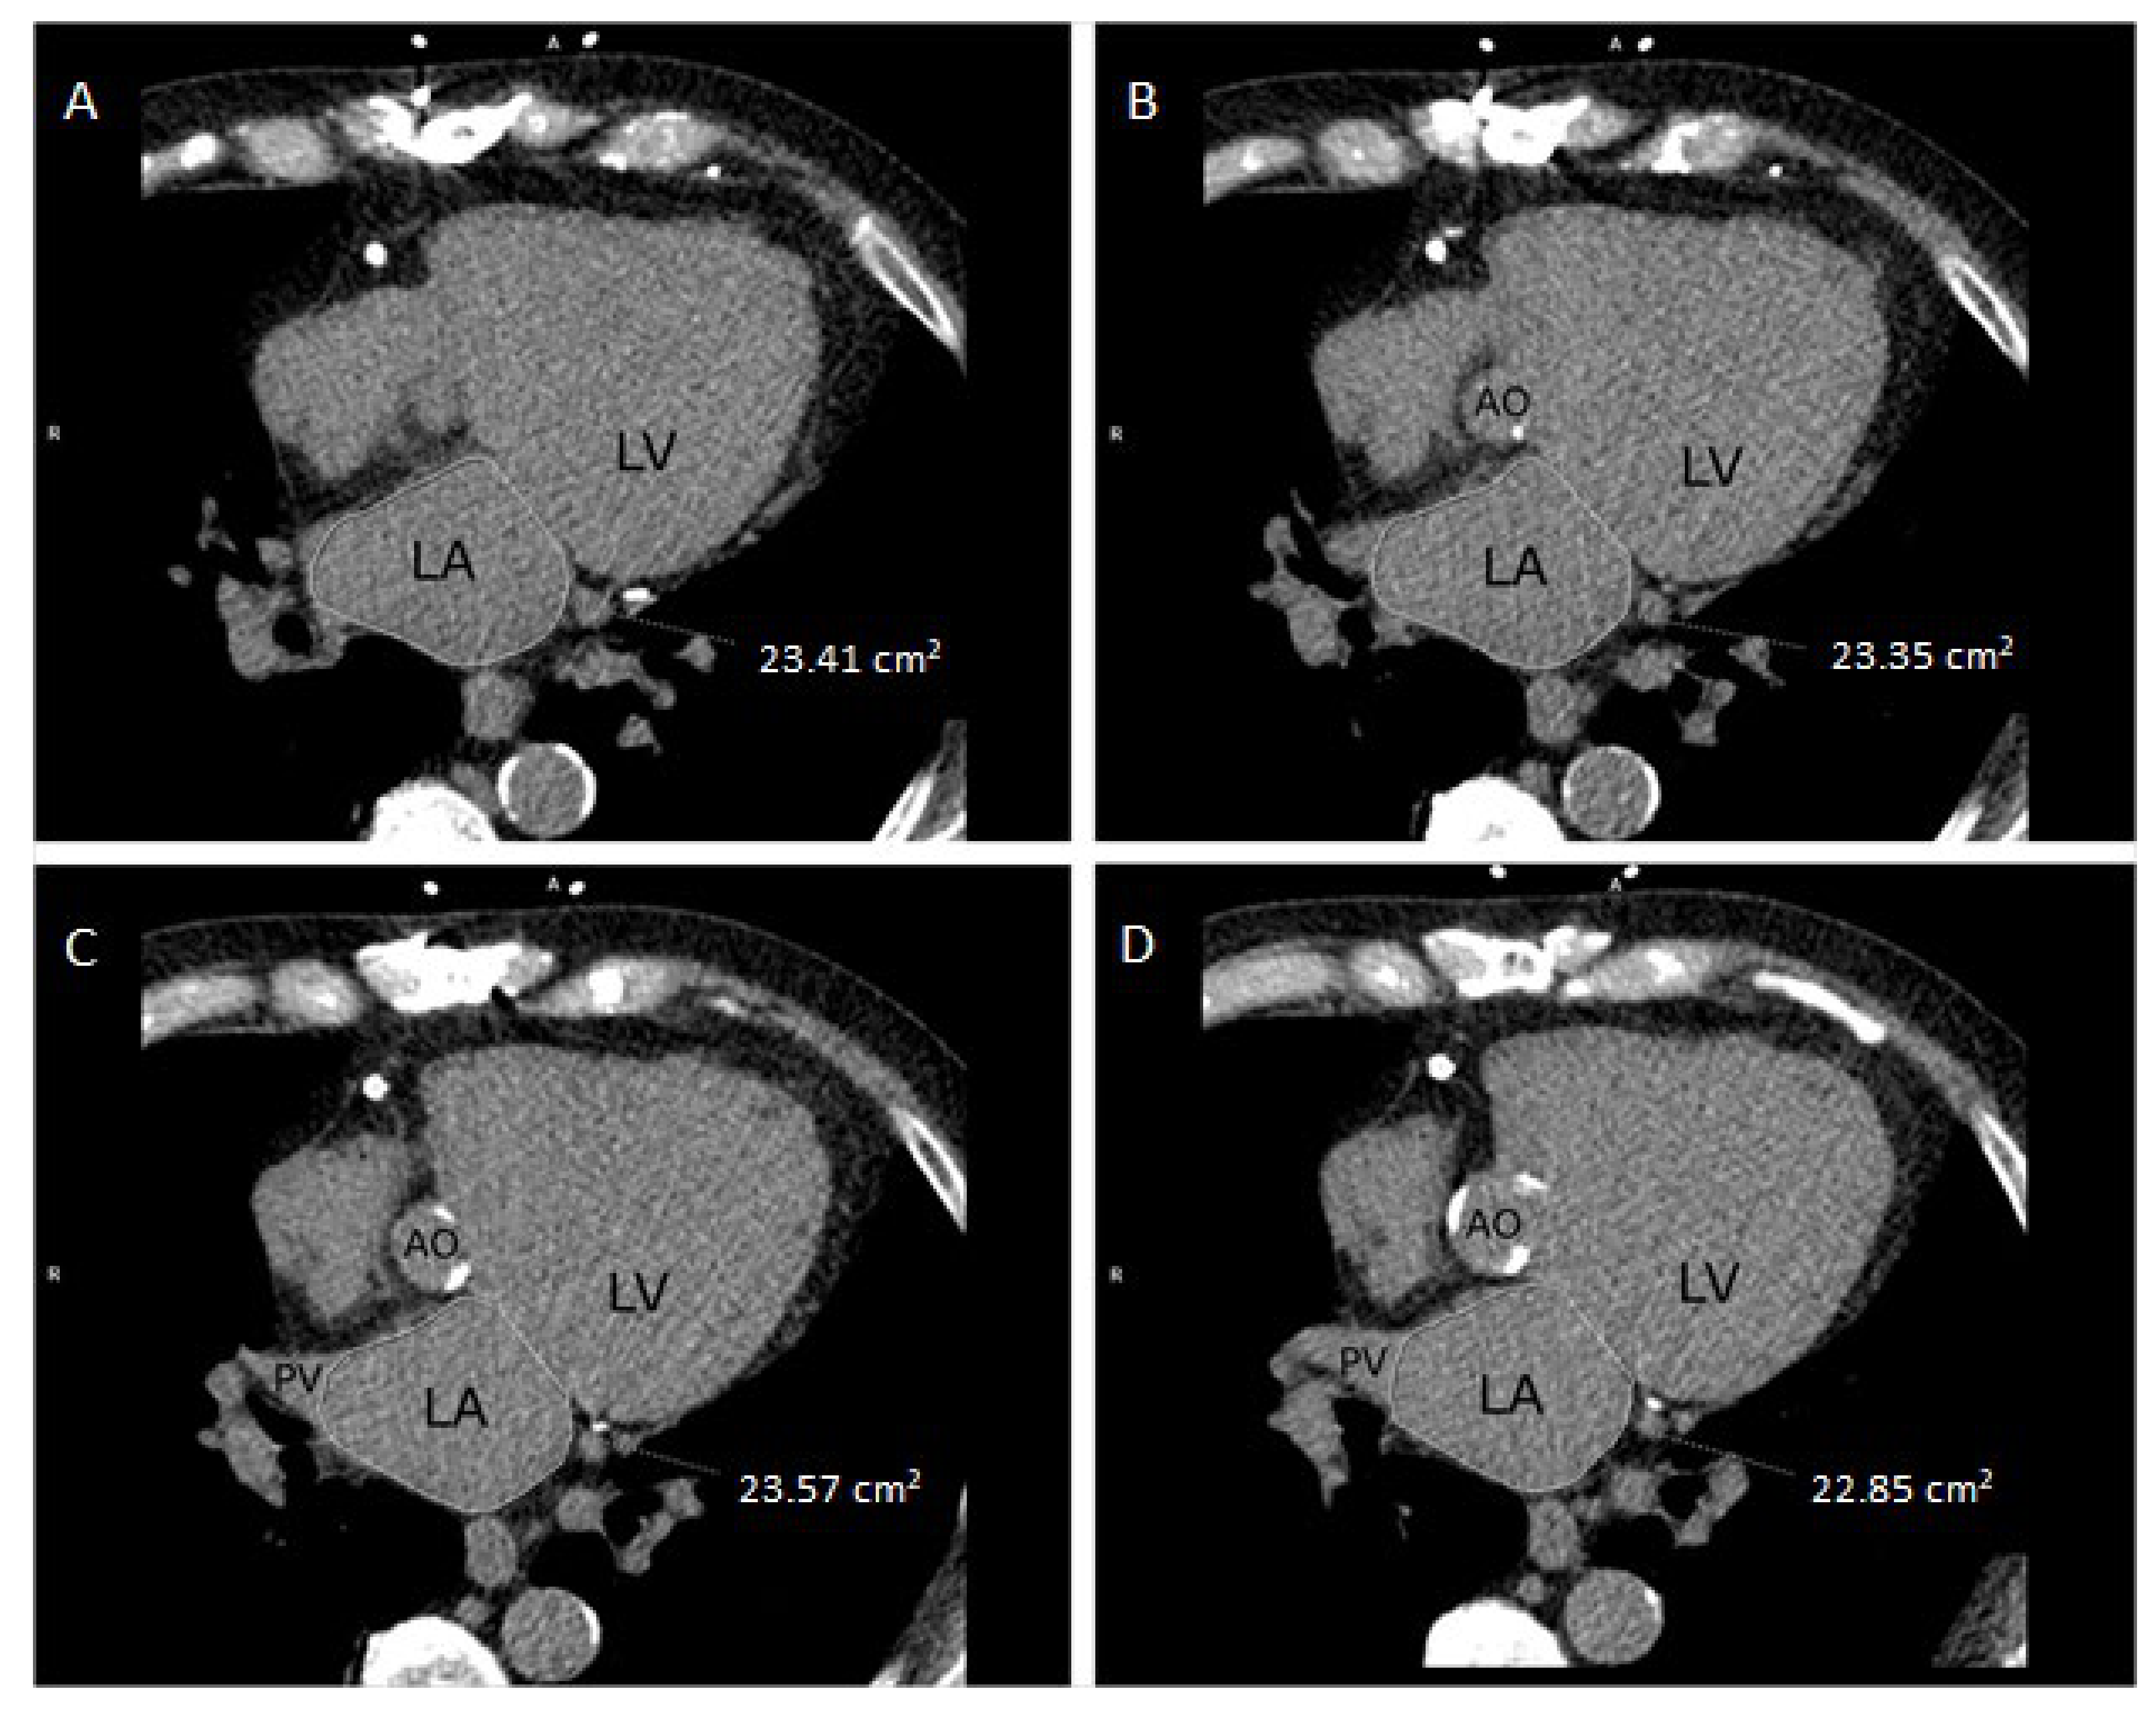

2.3. LA Size Measurement